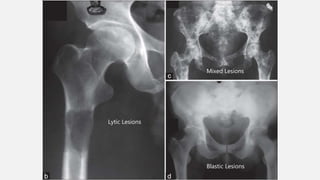

X-RAY IDENTIFICATION

• Lesion – Blastic/Sclerotic OR Lytic OR Mixed

• More commonly - Areas of bone production and bone

destruction

• Permeative, borders are ill defined

• Broken through the cortex => a Soft-Tissue mass

• Periosteal reaction - Codman triangle/Sunburst/Hair-on-end

appearance

Lytic Lesions

Mixed Lesions

Blastic Lesions

LYTIC VS BLASTIC LESIONS

• Prostate = Blastic/Sclerotic (induces bone growth)

• Breast = Mixed

• Kidney, Thyroid, Lung = Lytic (induces bone destruction)